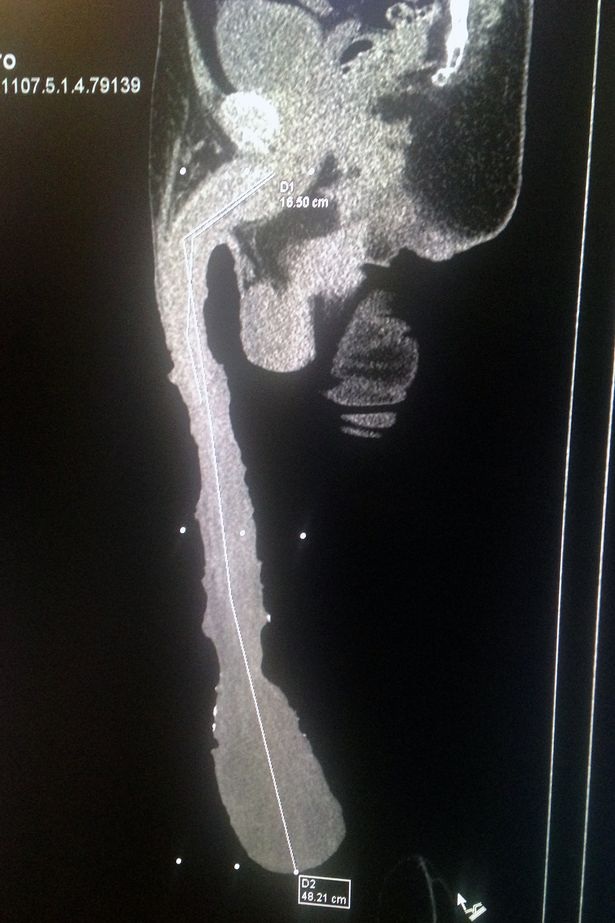

Theo Mirror, Roberto Esquivel Cabrera, 54 tuổi, có “của quý” dài tới 48cm. Ông nổi tiếng từ năm 2015.